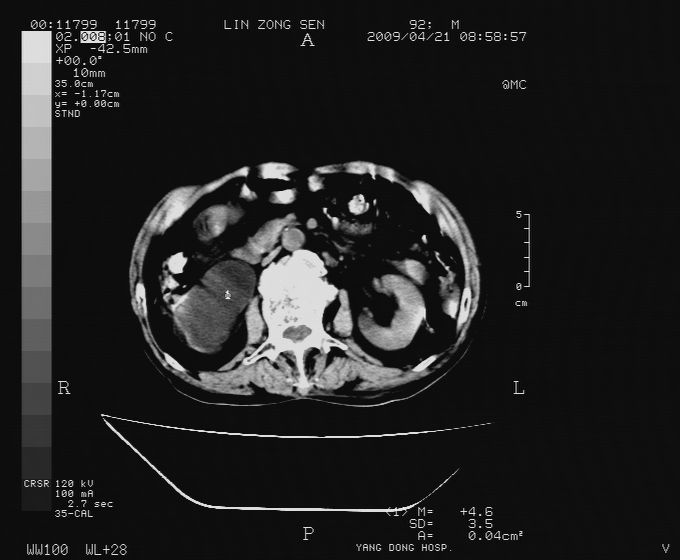

以下是引用卜一在2009-4-22 4:08:00的发言:[br]右肾积水伴输尿管上段积水!左侧肾多发囊肿!左侧腹壁软组织增厚,层次模糊,内密度较高—不排除血管瘤伴出血!